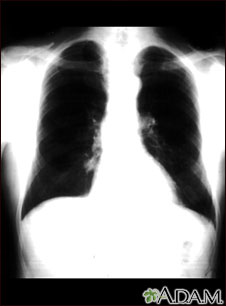

Lung nodule - front view chest x-ray

This is a chest x-ray showing a mass in the right lower lung near heart (seen on the left side of the picture).